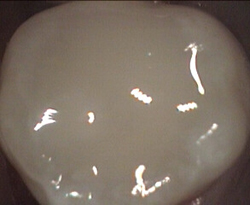

Unusual prevalent but superficial groove pattern on permenant molar after Sealed

unusual wide but superficial decay after